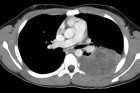

12 year old male presents for evaluation after undergoing recent workup for left sided chest pain.

Zoom image: Radiological image Radiological image.